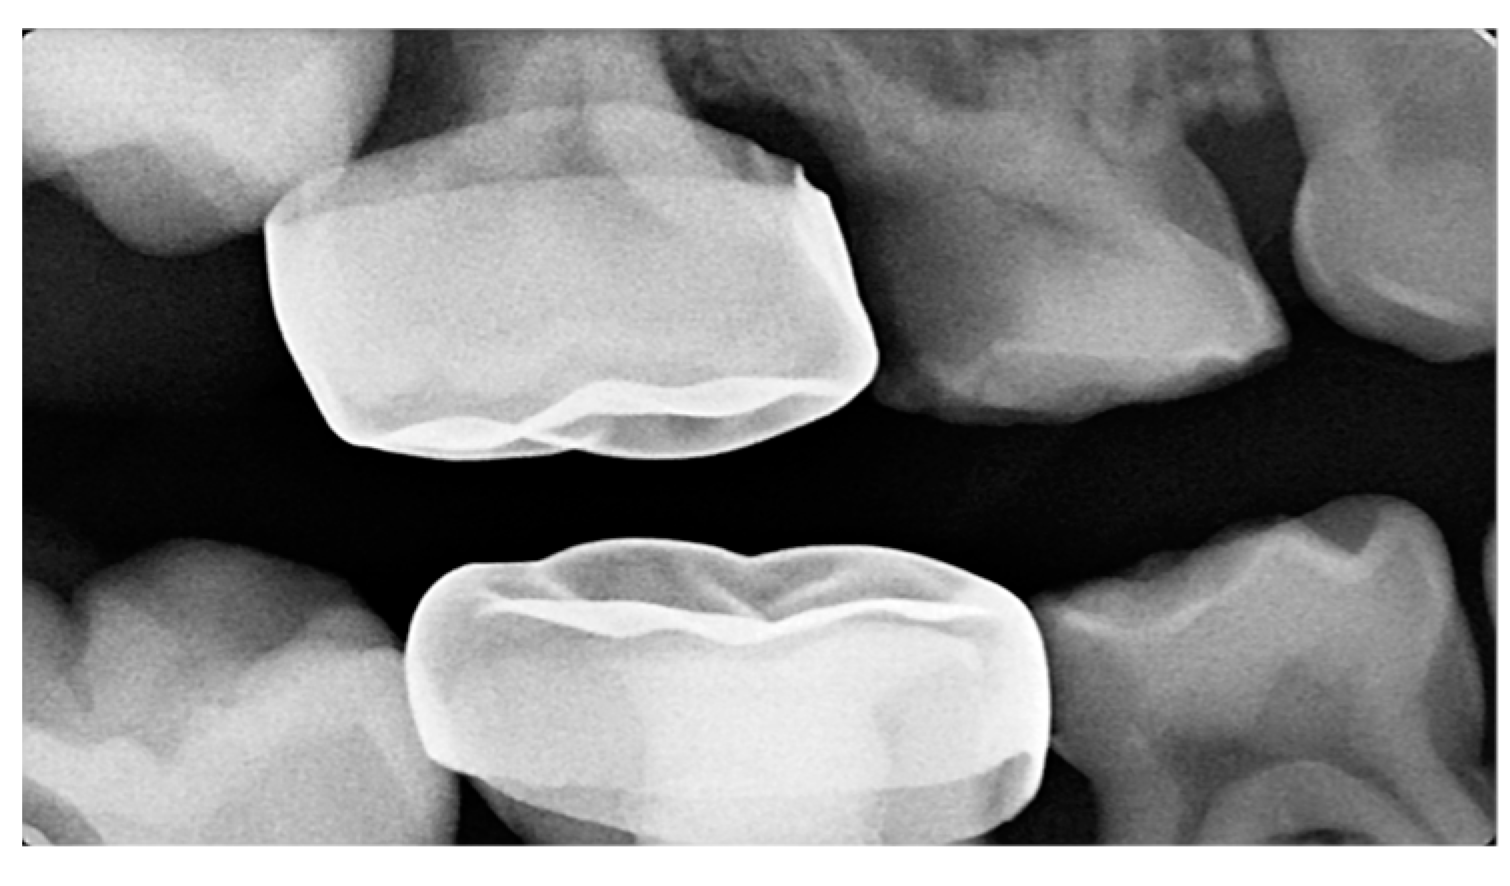

| Barberia-Leache ’s Classification (Based on the effect on second primary molar) * | |||||

| Grade 1 Mild | Grade 2 Moderate | Grade 3 Severe | Grade 4 Very severe | ||

| Limited resorption to the cementum or with minimum dentine penetration | Resorption of the dentine without pulp exposure | Resorption of the distal root leading to pulp exposure | Resorption that affects the mesial root of the second primary molar | ||

![]() | ![]() | ![]() | ![]() | ||

| Harrison and Michal’s Classification (based on severity of the lock using bitewing radiograph) * | |||||

| Normal | Minimal lock | Severe lock | |||

| No sign of impaction | Impacted less than half the width of the distal marginal ridge of the second primary molar | Impacted more than the width of the distal marginal ridge of the second primary molar | |||

![]() | ![]() | ![]() | |||